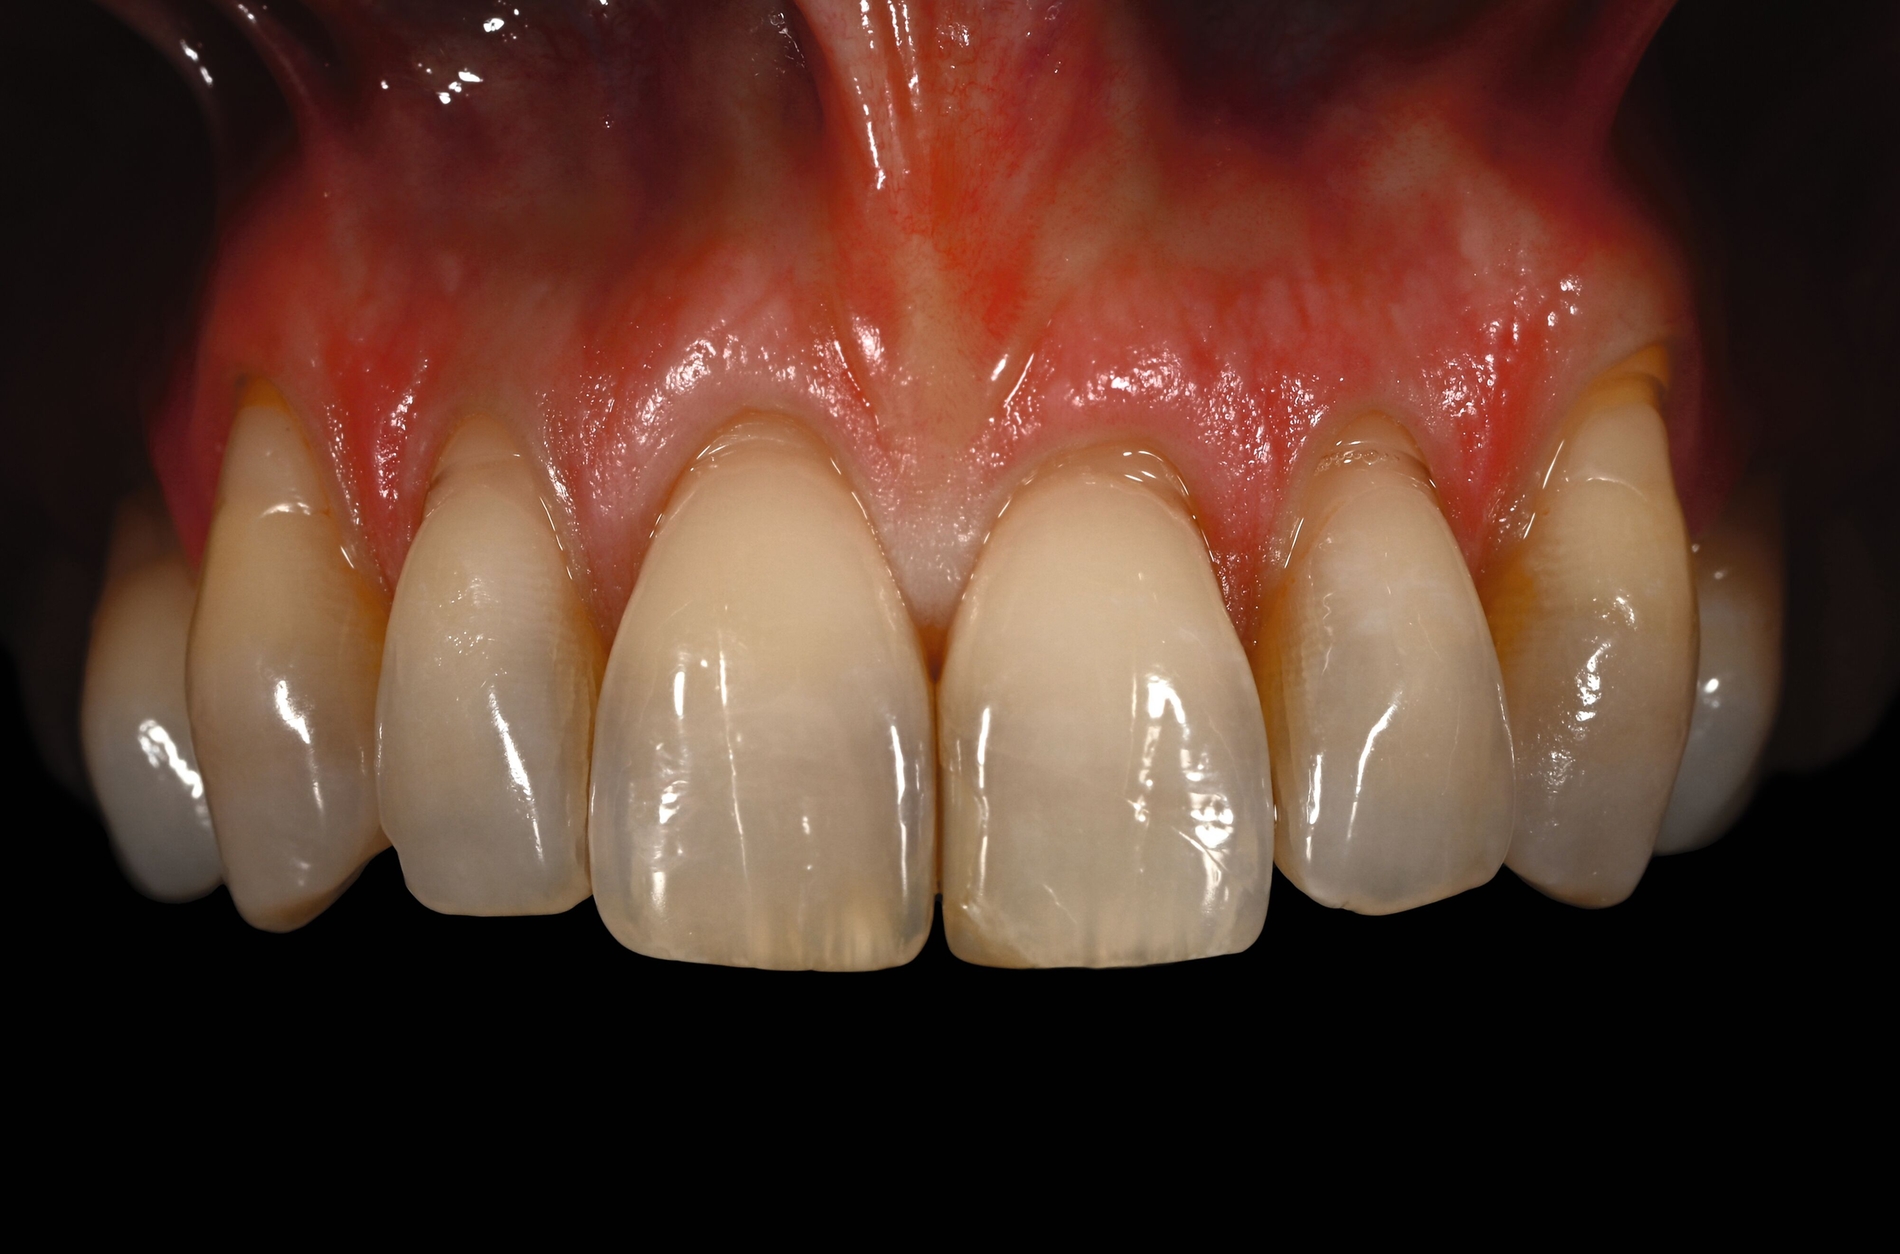

Trotz des Verbleibs des Epithels kann es zu sekundärer Wundheilung mit entsprechender Morbidität postoperativ kommen, besonders bei Techniken, die mehrere Inzisionen beinhalten, wie den sogenannten Trap-Door-Techniken, so dass sich die „Single-Incision-Technik“ durchgesetzt hat [Fickl et al., 2014]. Gegen eine übermäßige Blutung und postoperative Morbidität empfiehlt sich klinisch die routinemäßige Anwendung einer Verbandplatte, entweder in der Tiefziehtechnik oder präoperativ mittels eines Thermoplasts, so dass sich früh ein stabiles Blutkoagel bildet und die Wundheilung an der Entnahmestelle ungestört ablaufen kann. Dadurch wird die Morbidität klinisch deutlich reduziert. Das sBGT zeigt ästhetisch sehr gute Ergebnisse mit Blick auf Oberflächenstruktur sowie Farbe und kann unter anderem im Rahmen der Envelope- oder Tunneltechnik oder auch über einer Extraktionsalveole bewusst exponiert belassen werden, um zusätzlich befestigte Gingiva zu gewinnen.